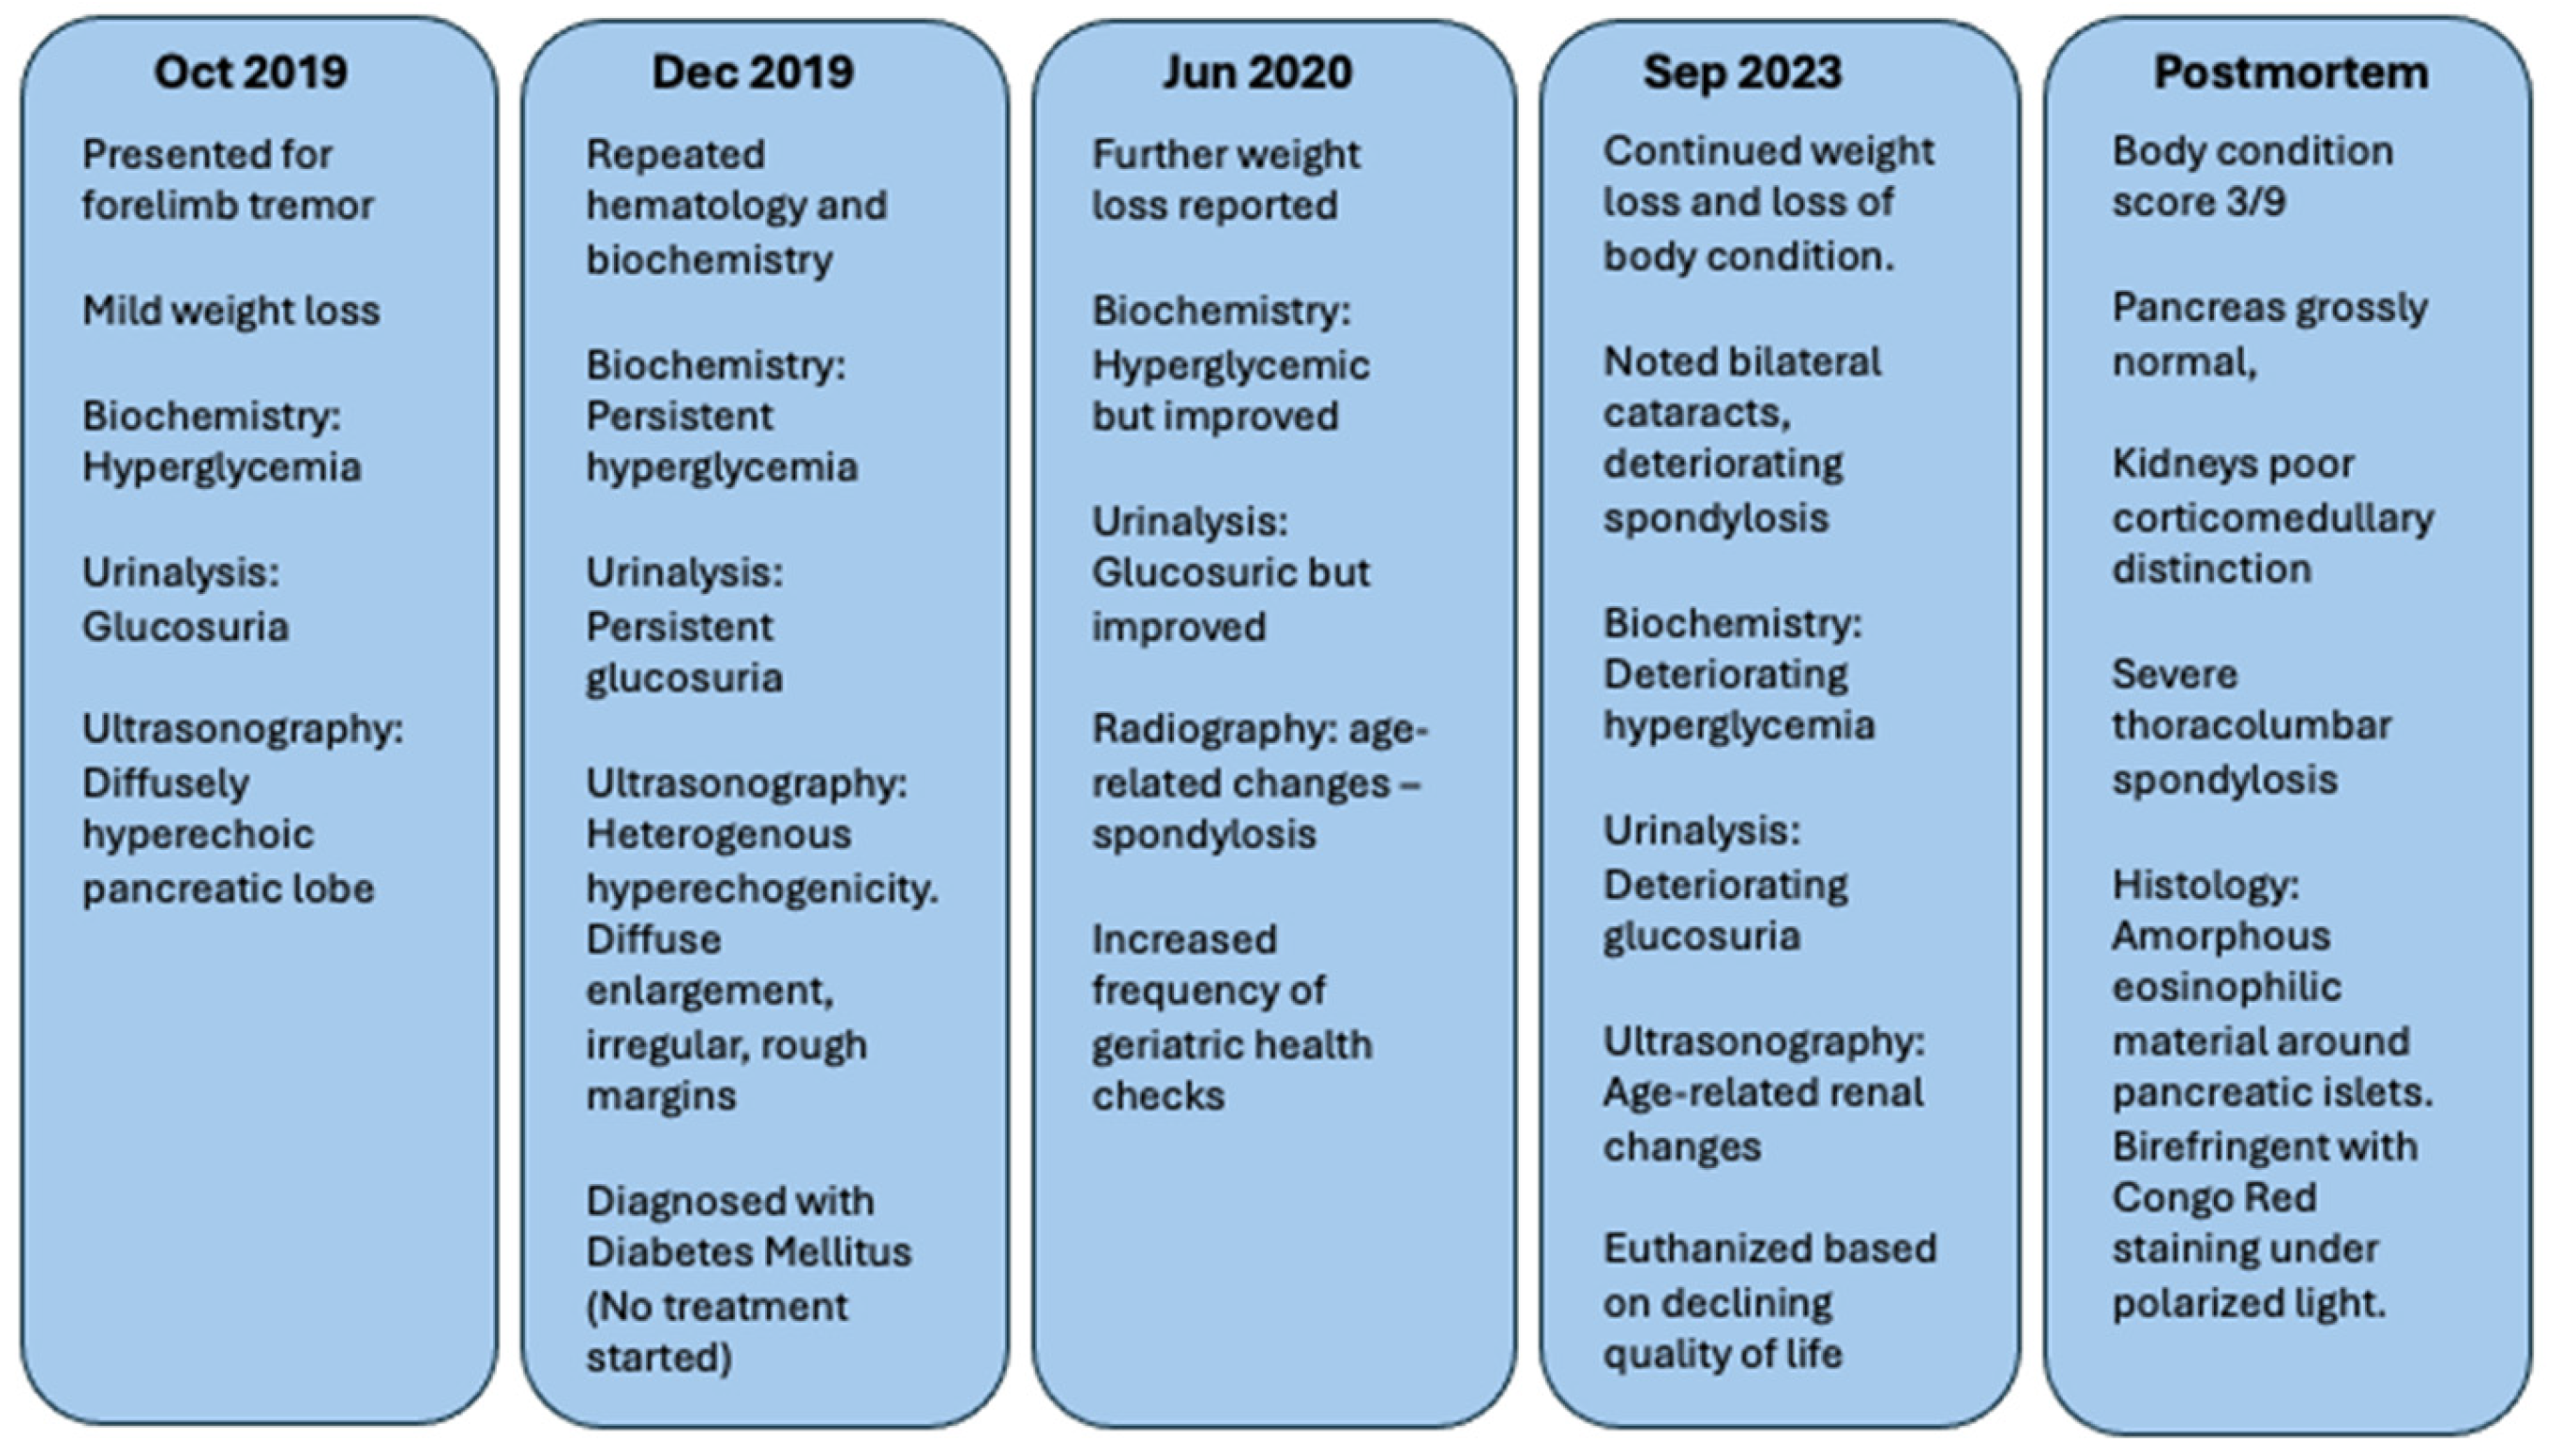

A 15.3 kg male binturong aged 16 years and 6 months presented on 10 October 2019 with tremors of the left foreleg, persisting over 4 days, as well as mild weight loss of 3.8% bodyweight over 2 weeks (

Figure 1). This patient was housed in an outdoor exhibit of approximately 400 m

2, with 24-h access to its indoor den, a building measuring approximately 3 m (l) × 3 m (w) × 2.5 m (h). The patient’s diet up until 2016 comprised mostly fruit but thereafter was adjusted to include a higher proportion of vegetables, better reflecting the species’ natural diet. Daily enrichment included the use of balls and toys in which food items were hidden, as well as numerous climbing structures within the exhibit.

Upon initial examination, a body condition score of 5/9 was assigned. Serum glucose was high (23.86 mmol/L; RI 2.93–18.94) (

Table 1), with concurrent glucosuria (approximately 500 mg/dL) (

Table 2). All hematology and biochemistry samples were run immediately following collection. All blood samples collected were drawn from either the patient’s cephalic or jugular vein under general anesthesia. To facilitate this, the patient was fasted for a minimum of 12 h, before sedation with 3 mg/kg of ketamine (Ketamine injection 100 mg/mL; Ceva Animal Health, Glenorie, NSW, Australia), 0.04 mg/kg of medetomidine (ilium Medetomidine hydrochloride 1 mg/mL; Troy Laboratories, Glendenning, NSW, Australia), and 0.15 mg/kg of butorphanol tartrate (Butomidor 10 mg/mL; Richter Pharma AG, Wels, Austria) administered intramuscularly. Testing was performed in-house using a ProCyte Dx Hematology Analyzer (IDEXX Laboratories, Inc. Westbrook, ME, USA) and a Catalyst One Chemistry Analyzer (IDEXX Laboratories, Inc. Westbrook, ME, USA), respectively. The Zoo Information Management System Global Reference Intervals (ZIMS, Species360, Bloomington, MN, USA) were used to obtain reference ranges for hematological and biochemistry values. As these reference ranges are updated monthly, reference ranges as accessed in April 2025 were utilized for the purpose of this report [

9]. All urine samples were collected by cystocentesis under general anesthesia and were analyzed immediately on collection. The gross appearance and urine specific gravity were noted for each sample. Cytology was performed using a wet mount preparation or stained with Diff-Quik for which findings were unremarkable. Samples were also analyzed in-house using urine test-strips (ABAXIS Global Diagnostics, Union City, CA, USA). We performed B-mode abdominal ultrasonography (MyLabEightVET Esaote S.p.A., Genoa, Italy), with the patient in dorsal recumbency. We used a convex-array ultrasound transducer (CA123, Esaote S.p.A, Genoa, Italy), noting the left lobe of the pancreas to be diffusely hyperechoic with smooth echotexture, and a chronic inflammatory process with associated saponification of the surrounding fat was suspected.

Bloodwork was repeated after 2 months (5 December 2019), in which hyperglycemia (27.71 mmol/L; RI 2.93–18.94) (

Table 1) and glucosuria (approximately >1000 mg/dL) (

Table 2) were found to be persistent. At this recheck, the binturong weighed 14.8 kg, and pancreatic changes suggestive of chronic fibrosis and suspected calcification within the pancreas were noted on ultrasonography. A generalized heterogenous hyperechogenicity and acoustic shadowing was reported in the pancreas, which appeared diffusely enlarged and irregular with rough margins (

Figure 2). A primary diagnosis of diabetes mellitus was established. Due to the logistical challenges associated with the administration of antidiabetic agents in zoological species, management at this stage was limited to changes in husbandry and diet, with increased frequency of monitoring by keepers and veterinary staff for the progression of clinical signs.

The patient re-presented 6 months later (26 June 2020) for further weight loss with a recorded weight of 13.35 kg. Although significant improvement was noted with respect to the observed hyperglycemia (14.22 mmol/L; RI 2.93–18.94) (

Table 1) and glucosuria (approximately 5 mg/dL) (

Table 2), radiography noted age-related changes such as marked spondylosis of the thoracolumbar vertebrae. The patient was scheduled for biannual regular geriatric health checks to monitor the progression of this potentially painful and debilitating condition closely.

A gradual loss of weight and body condition was noted in the patient over the following 3 years. During a geriatric health check performed on 6 September 2023, the patient was found to weigh 13.1 kg and we noted the development of further changes including bilateral cataracts, and significant progression of spondylosis. We discovered age-related renal changes on an ultrasonographic examination and performed repeat blood tests, finding a marked increase in hyperglycemia (36.18 mmol/L; RR 2.68–15.65) (

Table 1) and glucosuria (approximately 500 mg/dL) (

Table 2).

Given the difficulties associated with patient handling and medication, long term management with antidiabetic medication was not considered to be a viable option, and continued husbandry-related changes were deemed unlikely to be successful, given the concurrent age-related comorbidities. Regular veterinary evaluations for quality of life were performed over the following 3 months, and the patient was euthanized in December 2023 on welfare grounds.